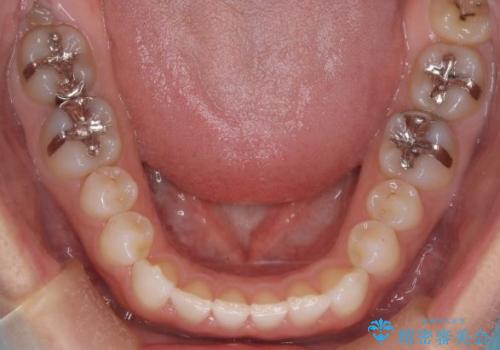

- 前歯の正中離開(すきっ歯)の改善を希望され来院された患者様です。

初診時の歯並びの状態としては、上顎中切歯間に1mm程の隙間があり、その他に見た目に関して気になるような問題点はない状態でした。

インビザライン(マウスピース)にて上顎のみの矯正治療を行いました。